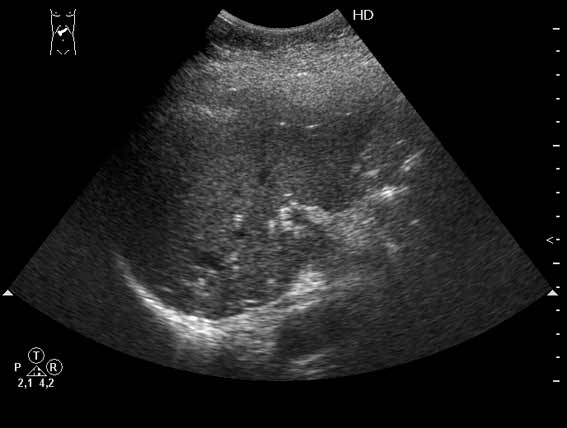

Внутрипротоковые гамартомы

Иногда встречается.

Как трактовать?

Быть может кто-либо знает о морфологическом субстрате подобного явления?

- 1.jpg (17.38 КБ) 6285 просмотров

- 2.jpg (11.96 КБ) 6288 просмотров

- 3.jpg (10.79 КБ) 6285 просмотров

Получил данные за то, что, видимо, это мелкие конкременты в протоковой системе.

Доводы:

1) Эхогенные структуктуры дают твинклинг-артефакт (twinkling), характерный, например, для кальцийсодержащих образований.

2) Все пациенты, у которых наблюдалась подобная картина страдали ЖКБ, у всех был удален желчный пузырь.